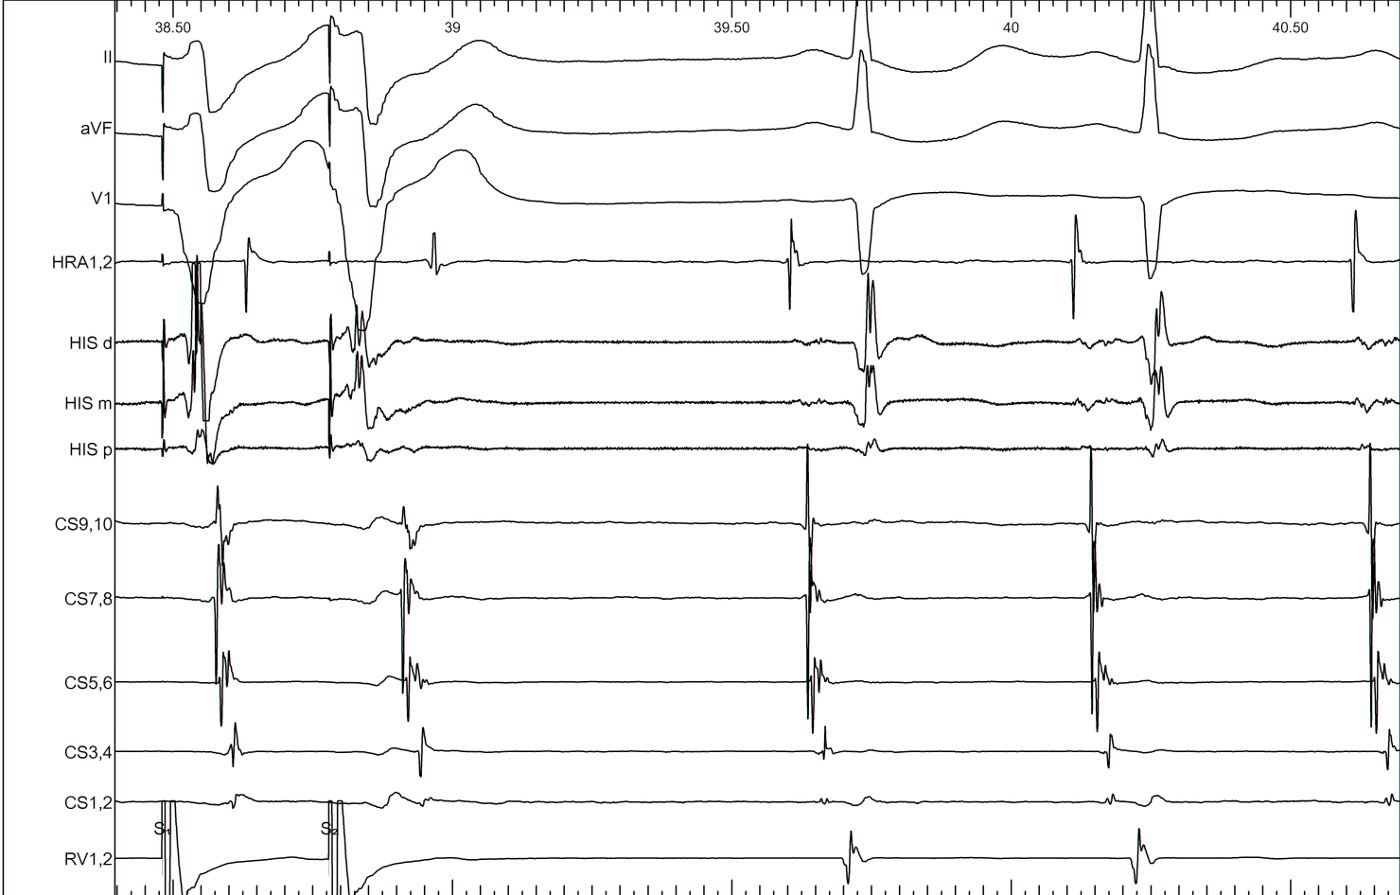

Narrow QRS tachycardia, central atrial activation, very short VA

typical_avnrt.jpg